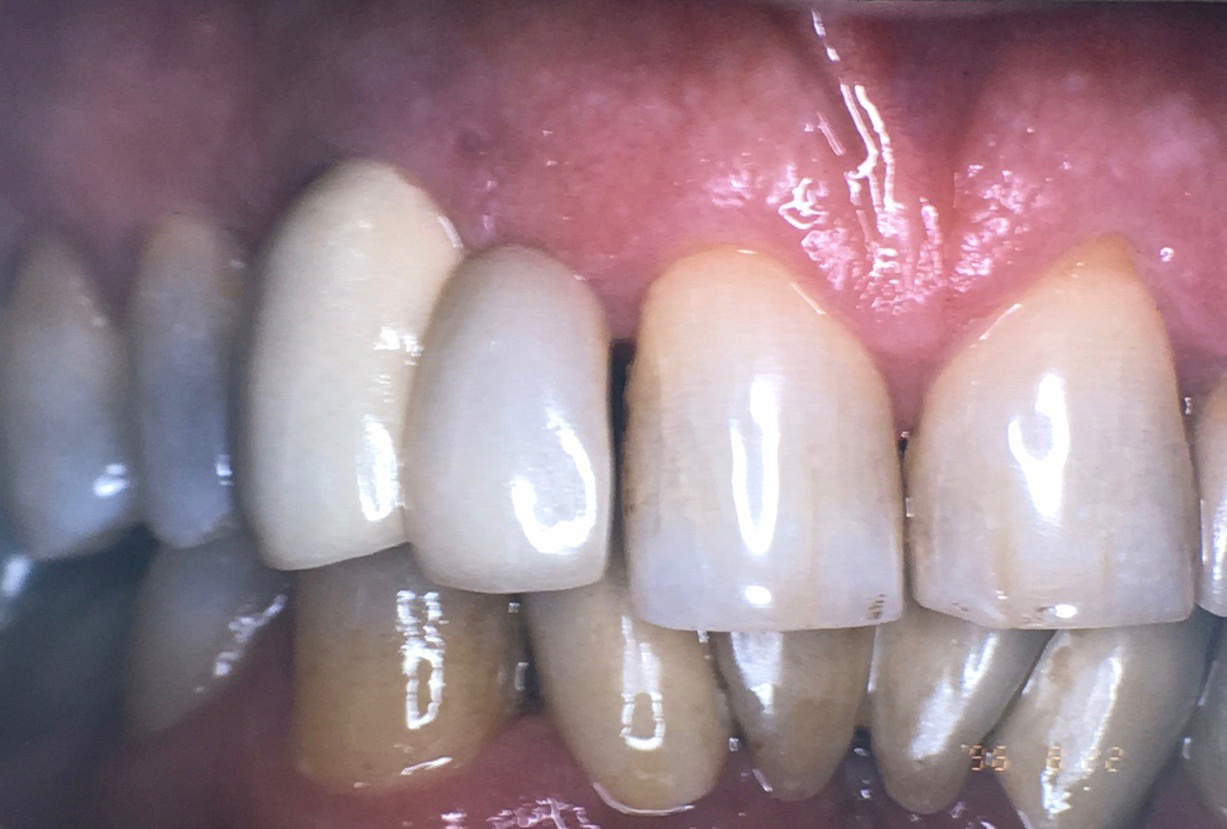

Fig 1. Chipping of veneering porcelain of porcelain-fused-to-gold full-arch fixed dental

prosthesis.

Figure 1

Fracture/Chipping of the Veneering Material

With 5-year complication rates from 3.2% to 25.5%,1 chipping of the veneering material (Figure 1) is the most common technical complication addressed in the literature.1,2 This can be minimized by designing the prosthesis before the final fabrication to ensure optimal framework design and thickness of the veneering material. Following basic occlusal principles in implant prosthodontics is essential. These include reduced cuspal inclination, narrow occlusal table, correction of load direction, reduced nonaxial loading, reduced length of the cantilever, and lighter occlusal contacts on implants.5 Restorations such as monolithic zirconia (Figure 2) and lithium disilicate are also being used to minimize chipping. However, long-term follow-up information on these restorations is limited.